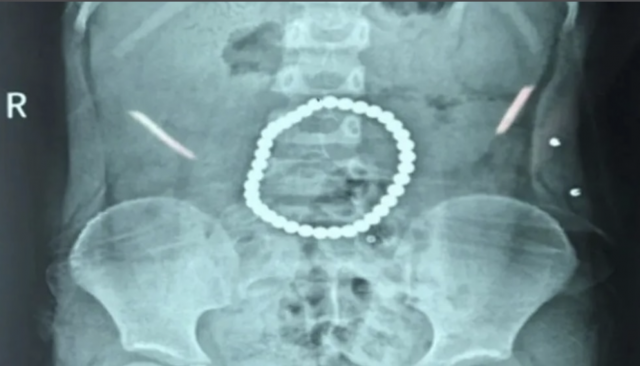

El artículo muestra los resultados de un estudio de series temporales cinemáticas de la marcha para dos grupos de pacientes (con Declive Cognitivo Leve y Enfermedad de Alzheimer Leve), y un grupo de sujetos de control pareados.